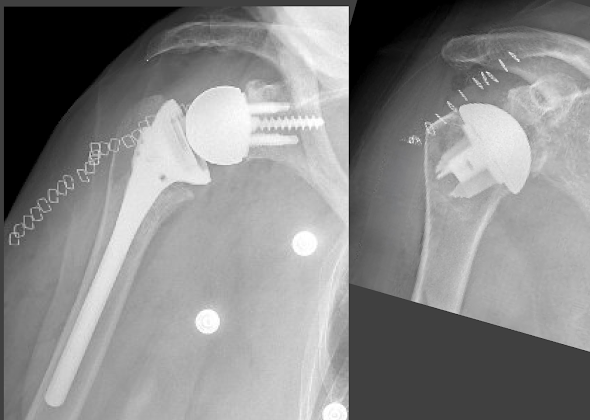

One of the most frequently debated topics in shoulder surgery is the choice between reverse total shoulder (RSA, below left) and anatomic total shoulder (aTSA below right) for patients having osteoarthritis with an intact rotator cuff.